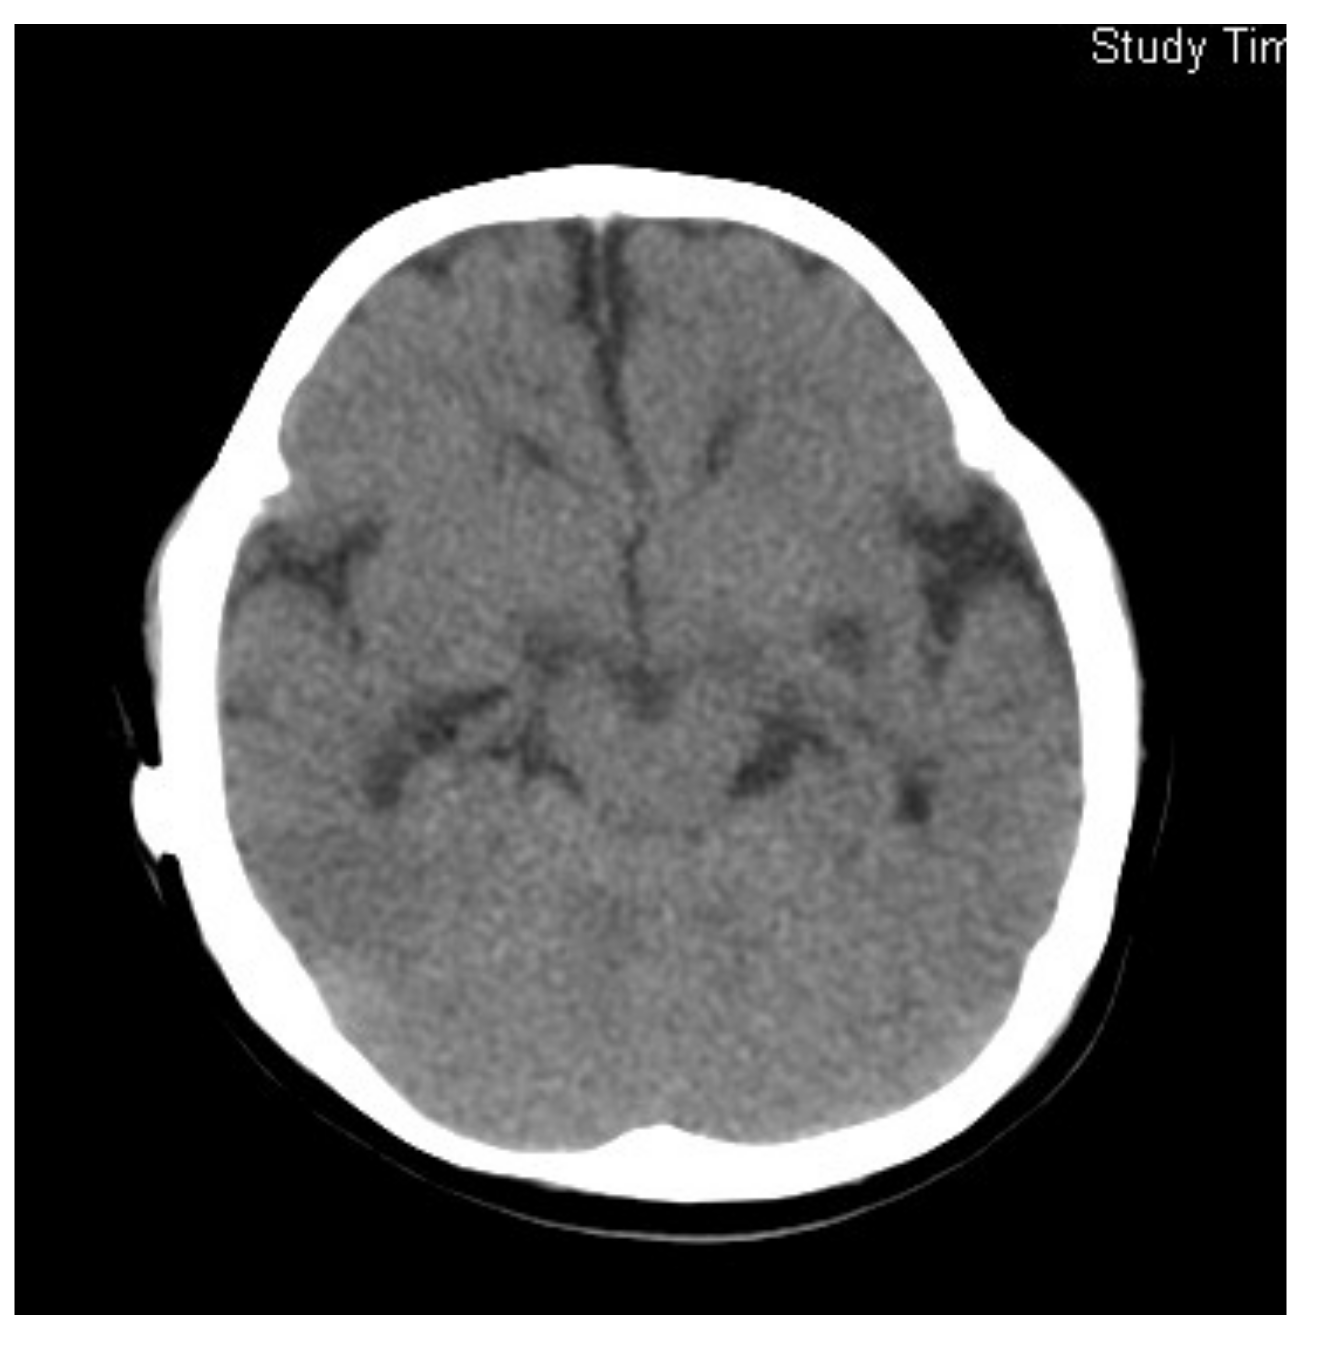

3.1. Case 1

3.2. Case 2

3.3. Case 3